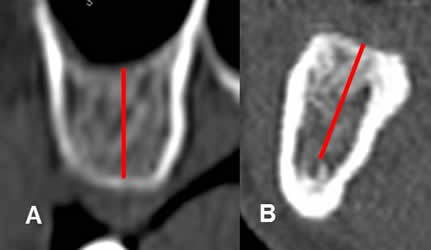

Fig 24. Altura de la cresta ósea.

A: TAC reconstrucción transversal del maxilar y B: de la mandíbula.

Altura del hueso, entre el borde superior e inferior de la cresta alveolar. En la mandíbula, el borde inferior corresponde al canal mandibular.

Fig 25. Ancho de la cresta ósea.

A: TAC reconstrucción transversal del maxilar y B: de la mandíbula. Ancho del hueso, medido entre los bordes internos de las corticales, en la región mas estrecha.

Fig 26. Inclinación de la cresta ósea.

TAC reconstrucción transversal de la mandíbula. Angulo de inclinación, trazado entre la vertical y el eje de la cresta ósea.